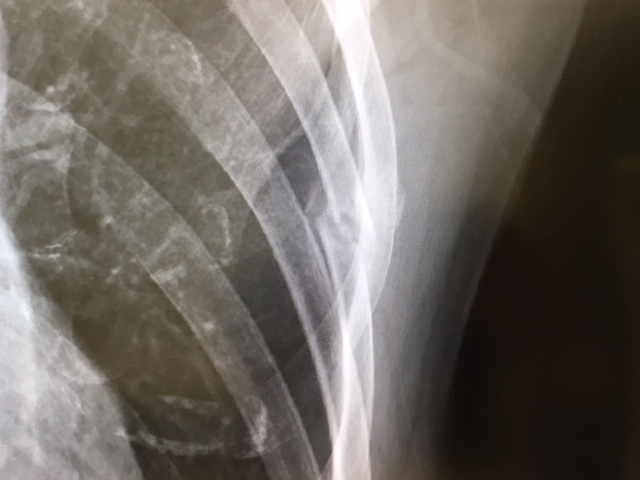

↓こちら、2ヶ月後。

相変わらずポッキリはポッキリのままなのですが、前回より「仮骨」がはっきりしてきています。ここまでくるとランニングをしても問題なし。3日ほど前からは腹筋の筋トレも少しづつ再開してますが、大丈夫ですね〜。

こうやって経過を見ると、ポッキリ折れてズレているところが元の位置に戻るわけではなく、それを覆うように仮骨が出来て、折れた部分も新しい骨に置き替わりながら全体的に太くなるような感じで治っていくというわけですね。レントゲンだとズレている部分に目がいって、折れたままやん!と思ってしまいますが、これで順調ということです(笑)。太くなった部分はどうなるのかというと・・・ネットなどで調べてみたところ、何年かかけて吸収されていって、徐々に元の太さに近づいていくらしい。